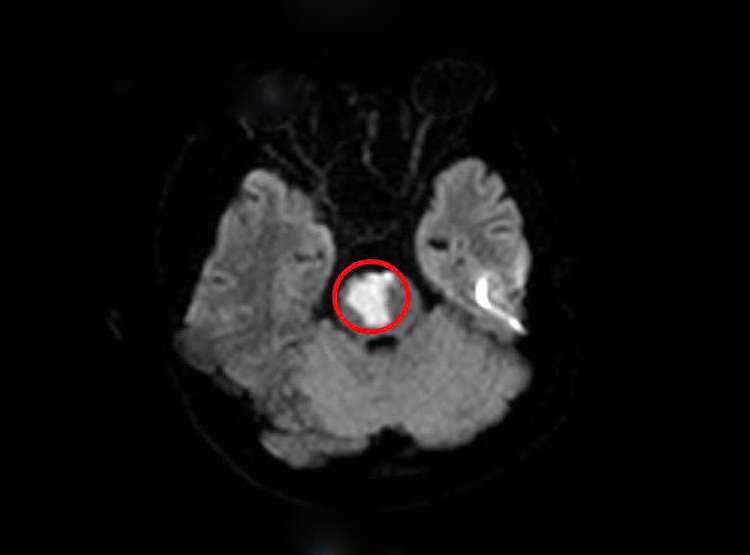

After taking the medical history, doctors suspected a stroke and ordered a brain MRI.

The results revealed a cerebellar and pontine infarction caused by a blockage in the basilar artery.